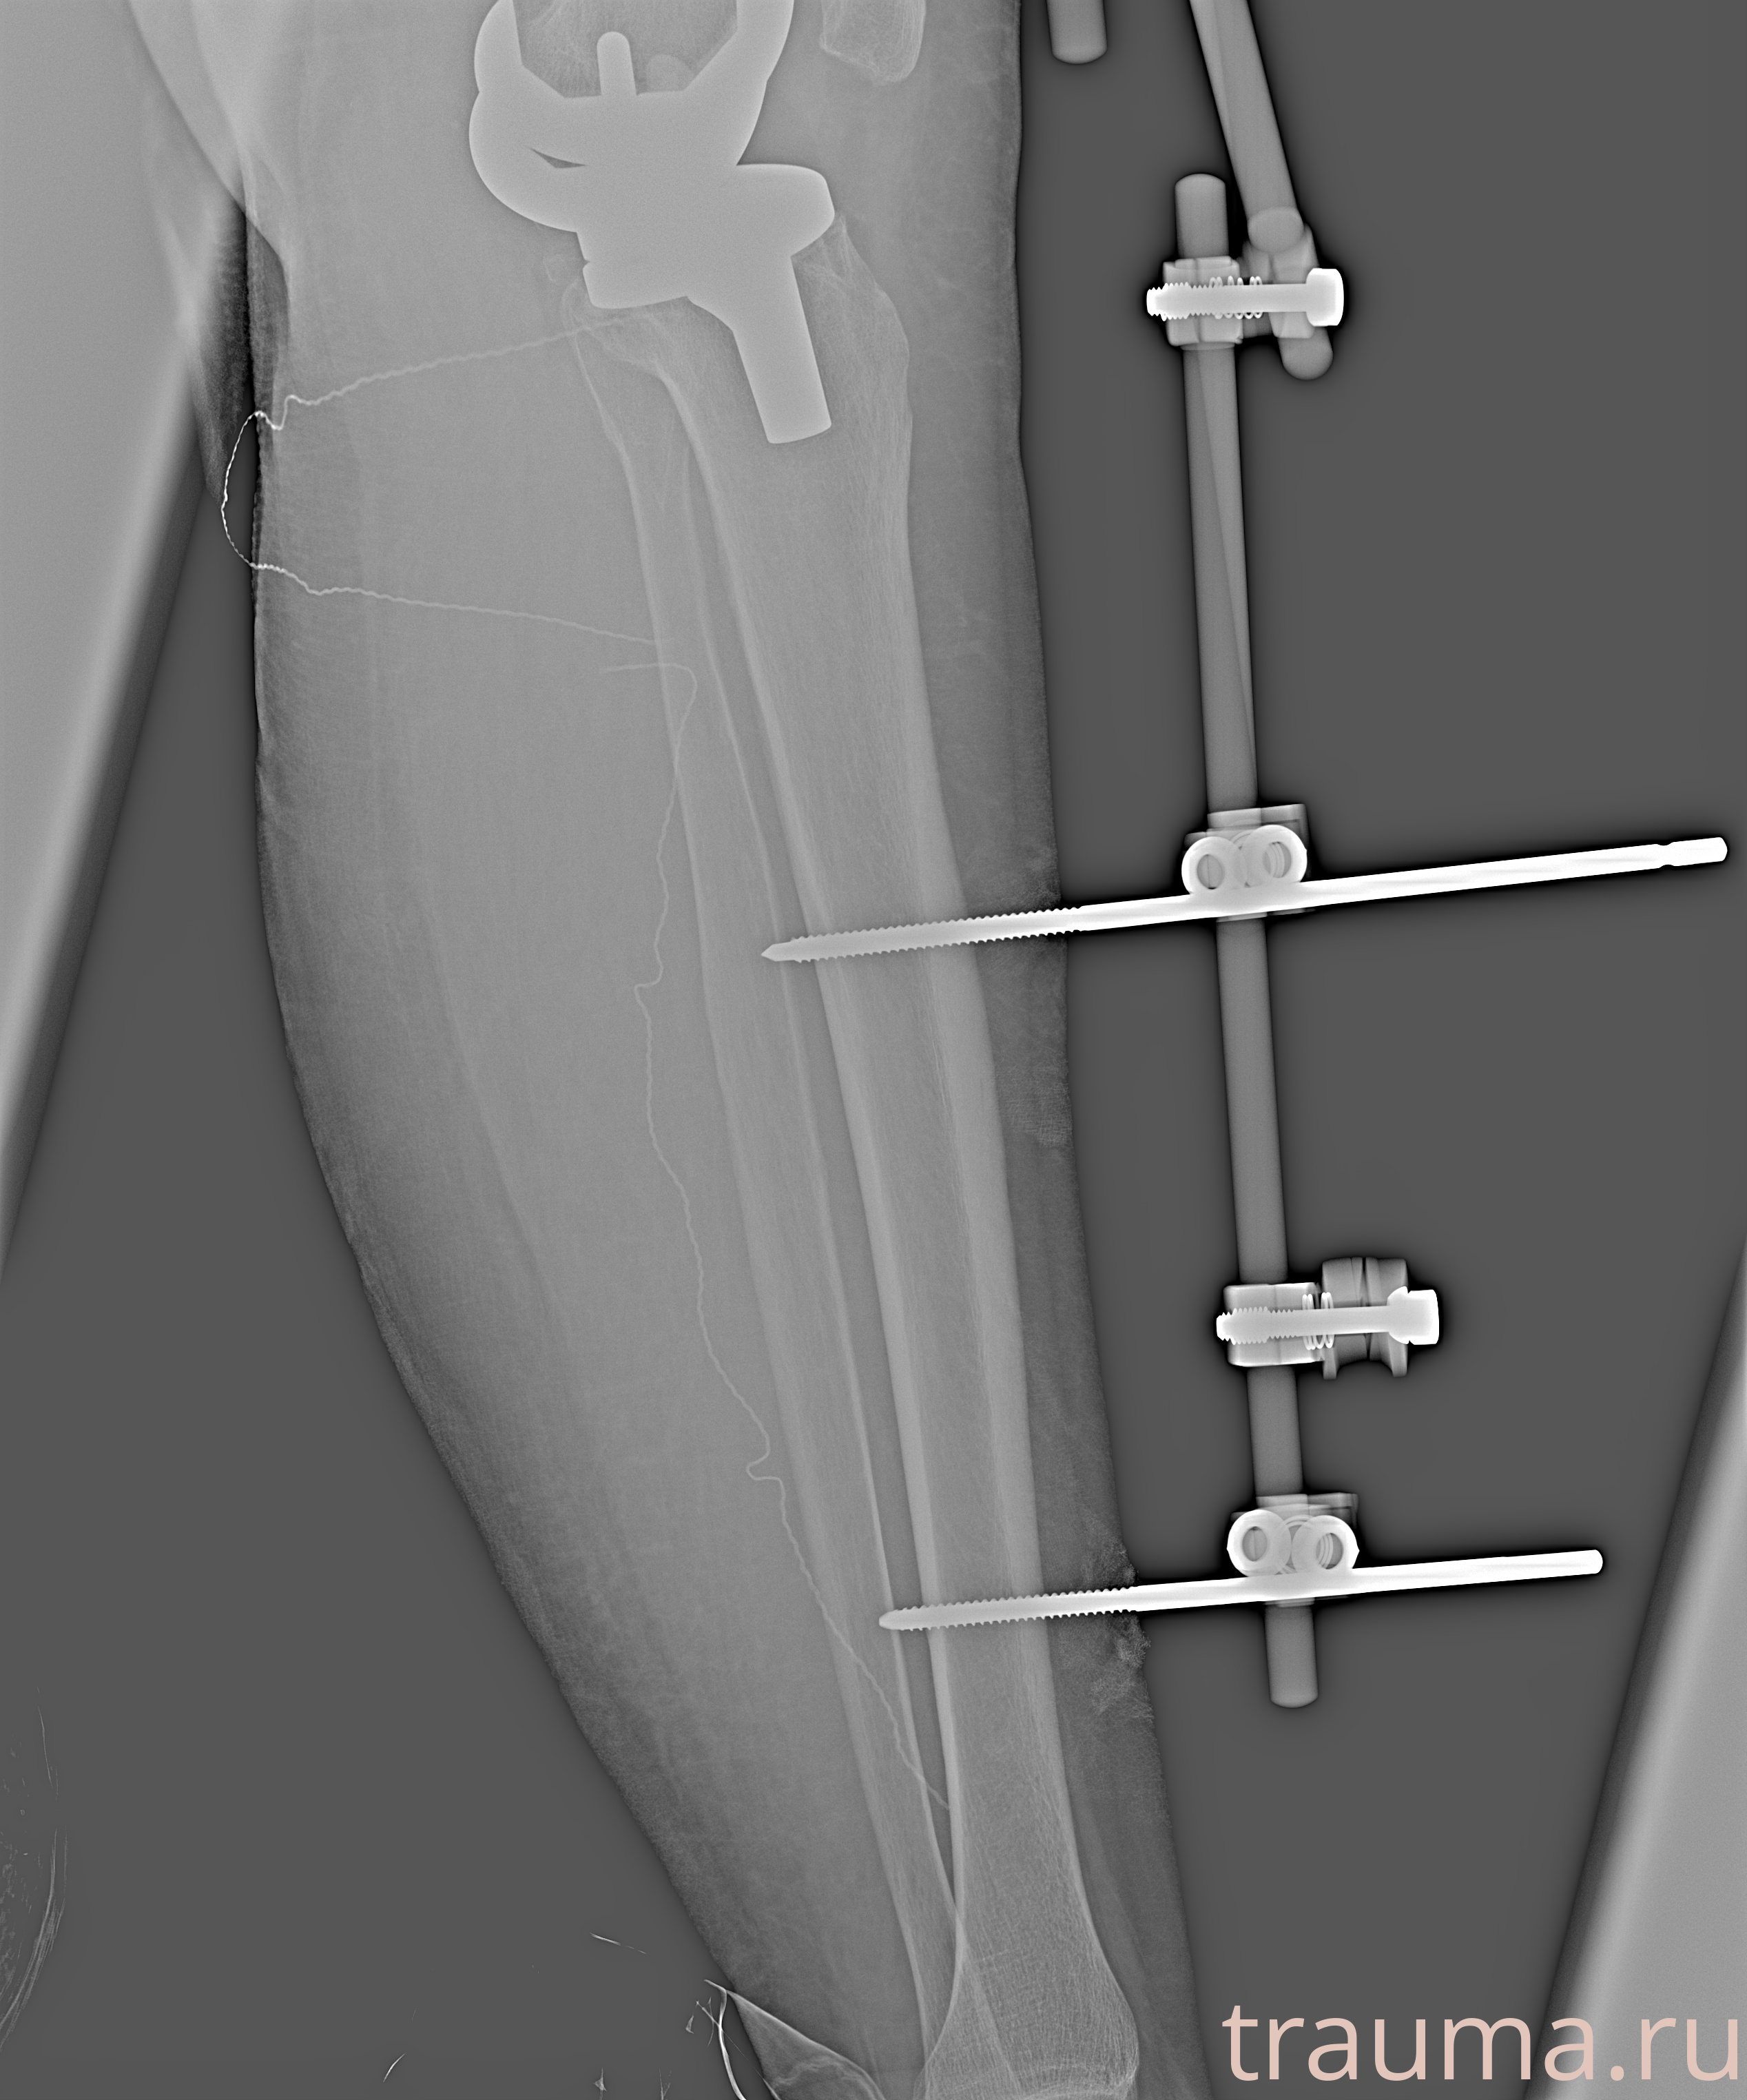

Видео КТ после вправления и наложения АНФ